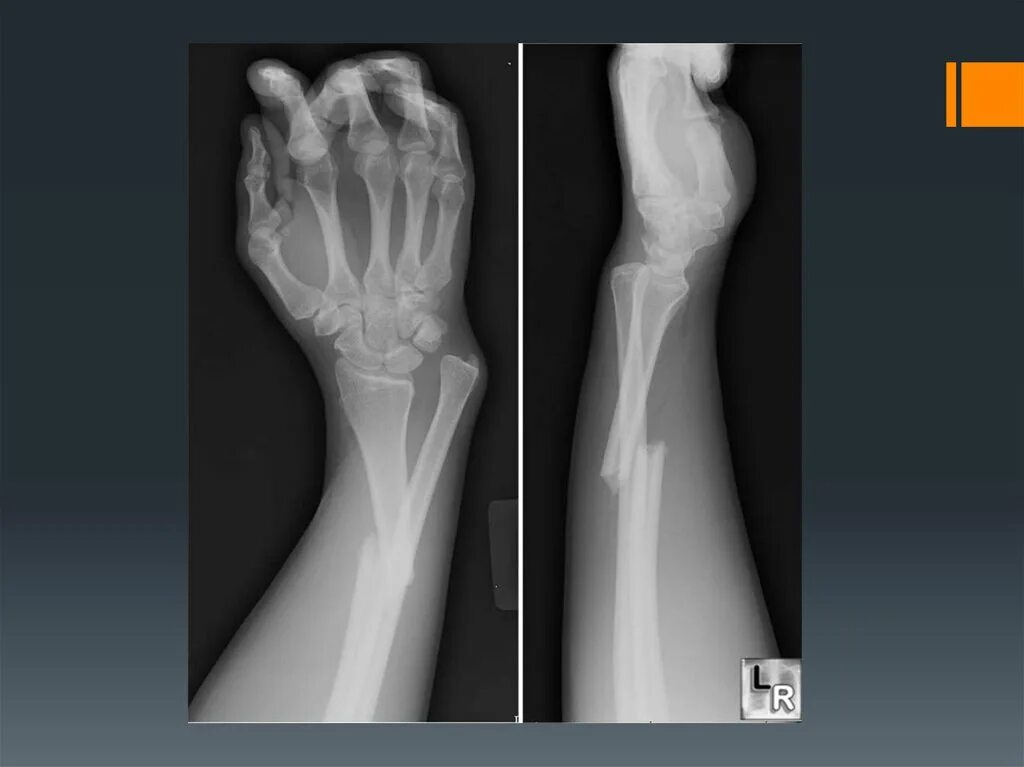

Открытые и закрытые вывихи